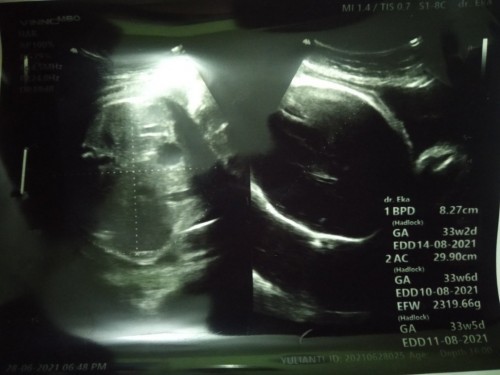

Bun ada yang sama gak sekarang saya lagi hamil 33week tapi kepala janinnya masih diatas😟 dari sebulan yang lalu udah sering senam sujud terus tak coba pake musik klasik ,udah jjp sama jjs juga tapi tetep aja si dedenya anteng banget kepala diatas gak mau kebawah😟 Dan setiap selesai senam sujud si dedenya bukannya muter kebawah malah tambah ke atas kepalanya😟😟 Gimana ya bun caranya biar si dedenya mau kebawah kepalanya?😟😟 #seriusnanya #bantusharing #ingintahu #jangandibully #jangandibully #jangandibully #pleasehelp #firstbaby